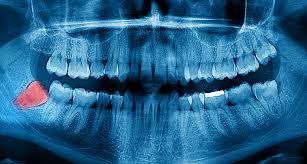

사랑니는 우리가 일반적으로 부르는 명칭이고, 정확한 이름은 제3대구치이다. 이름 그대로 세 번째 큰 어금니이다. 어금니는 작은 어금니(소구치) 두 개와 큰 어금니(대구치) 세 개가 있다. 제3대구치는 치열의 가장 마지막, 구강 내에서 가장 안쪽에 위치한 치아이다.

우리의 입 안에는 위턱의 좌·우측과 아래턱의 좌·우측에 각각 하나씩 총 네 개의 사랑니가 있다. 사랑니도 다른 치아들과 마찬가지로 음식물을 분쇄하여 소화를 돕는 역할을 한다. 다만 총 32개의 치아가 들어앉기에는 턱이 상대적으로 작은 사람들이 많다. 결국 다른 치아들이 다 올라오고 나서 마지막에 나는 사랑니가 차지할 공간이 부족한 경우가 생긴다.

부족한 공간을 비집고 올라오는 사랑니는 정상적인 치열에서 벗어나거나 공간이 전혀 없는 경우 그냥 턱뼈에 묻혀 있게 된다. 정상적인 위치로 올라오지 못한 사랑니는 구조적으로 음식물이 자주 끼고 칫솔질로도 청결을 유지하기 어렵다. 잇몸에 쉽게 염증이 생기고 사랑니 앞 치아에 충치가 자주 생긴다.

반복적으로 발생하는 염증은 사랑니와 주변 치아까지 심한 치주염과 구취를 유발한다. 구강 내로 올라오지 못하고 깊게 매복되어 있는 사랑니는 드물게 함치성 낭종, 법랑아 세포종처럼 턱뼈 안에 물혹이나 양성종양을 발생시키기도 한다.

사랑니가 턱뼈에 심하게 매복되어 있는 경우 사랑니를 감싸고 있는 치낭에 물이 차게 되어 낭종이라는 물혹으로 변성되어(함치성 낭종) 건강한 악골을 녹이거나 다른 치아의 위치를 변화시킬 수 있다. 이러한 함치성 낭종은 방치된다면 악골의 골절이나 골수염, 양성종양으로 발전할 수 있다.